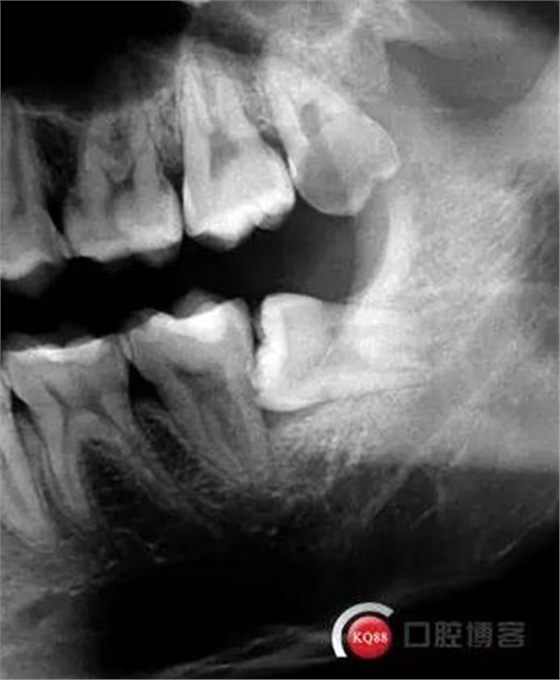

檢查:口內(nèi)可見38未完全萌出,無松動(dòng),周圍牙齦顏色正常,叩診(—)觸診(—),X線顯示近中阻生,雙根

診斷:阻生齒

治療方案:建議拔除